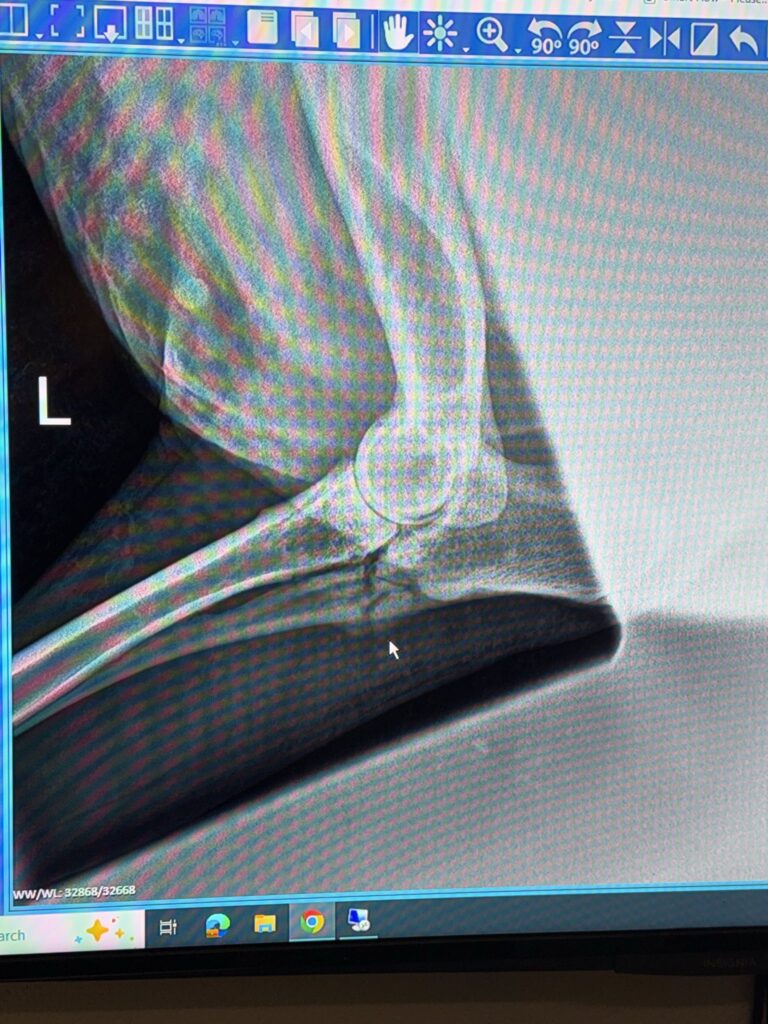

An X-ray image from another angle clearly showed the problem: Annie has a fracture in her ulna, just below the joint. There are visible signs that her body has been trying to heal itself for some time, which, again, isn’t surprising, as she’s been on stall rest due to her leg bothering her. Even though her body has been trying to heal, it’s very unlikely that this kinda of fracture will ever heal on its own.

What they can’t say for sure is how Annie’s fracture happened. One possibility is a pathological fracture, meaning the bone broke not because of a major injury, but because the joint was already compromised. Advanced arthritis can limit normal movement, change how force moves through the joint, and place increased stress on nearby bone. In that situation, a routine, low-impact movement—such as standing, turning, or shifting weight—can be enough to cause a fracture, even without a fall or obvious trauma, and injuries like this often can’t be traced to a single moment.